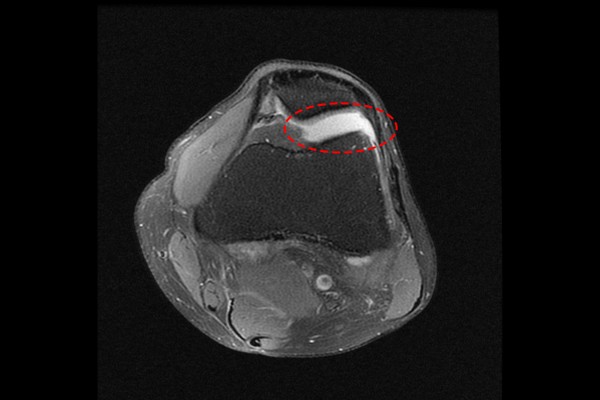

환자분의 상태를 자세히 파악하기 위해서 MRI 검사를 시행하였고, 먼저 좌측 무릎의 MRI를 보시면 무릎 관절내에 두꺼운 추벽이 확인되는데, 추벽이 균일해 보이지 않고 무릎 뼈 사이에서의 충돌로 인하여 손상이 될 가능성이 있어보입니다.